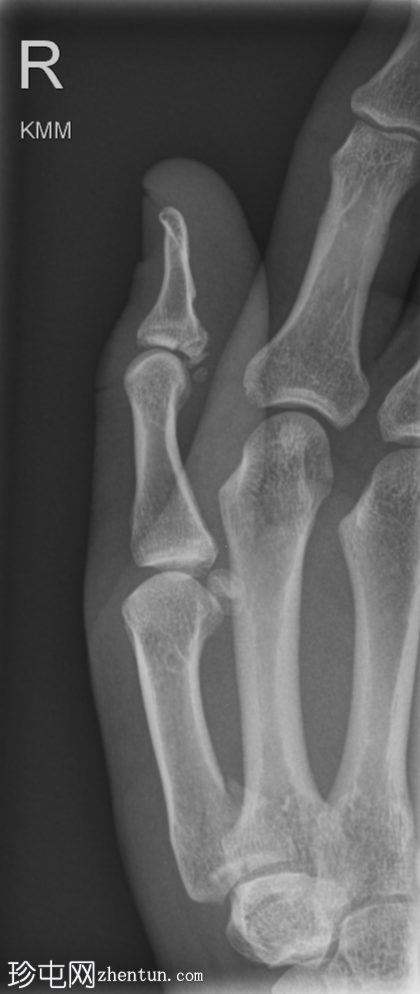

侧位

右拇指远节指骨掌侧关节内轻度移位骨折,可能为撕脱性骨折。关节内可见轻微皮质台阶。

第一掌骨基底部可见轻微移位骨折,根据骨折轨迹推测可能为关节内骨折,但关节内皮质台阶不明显。若临床治疗方案改变,可能需要进一步

影像

学检查。第一腕掌关节解剖对位良好。